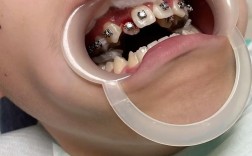

- 患者配合: 保持良好的口腔卫生,避免因炎症影响牙周健康;遵医嘱避免咬硬物,保护矫治器。